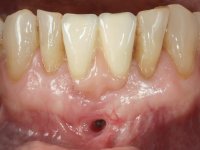

A paciente surgiu na consulta referindo que tinha aparecido um “buraquinho” na zona da gengiva junto a um implante. Não referiu ter tido dor nem qualquer tipo de tumefação.

Paciente do sexo feminino com 62 anos, fumadora. 10 Anos atrás tinha sido colocado um implante na zona dos dentes 41 e 42 para reabilitar com uma ponte de dois elementos a falta destes dois dentes. Feito o exame imagiologico foi observada uma perda óssea junto ao implante compatível com uma peri-implantite. A parede óssea vestibular junto ao implante apresentava uma extensa reabsorção, estando a superfície vestibular do implante em contacto com os tecidos moles e numa determinada zona um orifício permitia a visualização do implante através do tecido gengival. Os dentes 42 e 32 apresentavam já alguma mobilidade.

Após estudo imagiológico foi planificada a colocação de dois implantes de 3.3 mm de diâmetro e 10 mm de comprimento. No dia da cirurgia foram extraídos os dentes 42 e 32 e removido o implante. Os implantes foram colocados na zona dos alvéolos tendo o cuidado de lingualizar um pouco o seu posicionamento. Foi feita uma impressão pela técnica de moldeira aberta com o retalho aberto para a confeção da ponte provisória imediata. Enquanto a impressão foi para o laboratório, foram colocados parafusos de cicatrização altos e feita a sutura da ferida cirúrgica. A paciente esperou 2 horas na sala de espera enquanto no laboratório era confecionada a ponte provisória. A ponte provisória imediata aparafusada foi colocada e o seu assentamento controlado imagiologicmente. Passados 3 meses foi realizada a impressão definitiva com uma técnica de moldeira aberta. Nessa consulta aproveitamos para polir a ponte provisória com taças de borracha para que os tecidos moles pudessem maturar em melhores condições. Foi feita a recolha de informação para caracterizar da melhor forma a estrutura monolítica em Zr. Foram utilizadas guias de cor para a cerâmica de tonalidade coronária e gengival. No laboratório foi confecionada uma ponte em Zr. aparafusada que foi cuidadosamente caracterizada. Após aprovação pela paciente foi colocada definitivamente em boca. O aperto foi feito com uma chave dinâmica com 35 N de torque. Os orifícios foram tapados com teflon e obturados com resina composta.